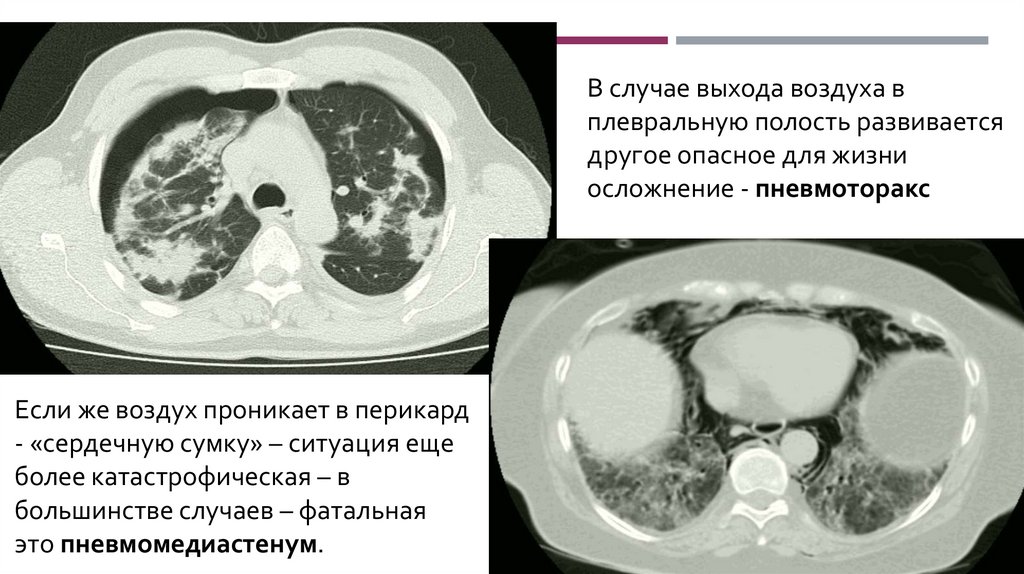

В случае выхода воздуха в

плевральную полость развивается

другое опасное для жизни

осложнение - пневмоторакс

Если же воздух проникает в перикард

- «сердечную сумку» – ситуация еще

более катастрофическая – в

большинстве случаев – фатальная

это пневмомедиастенум.